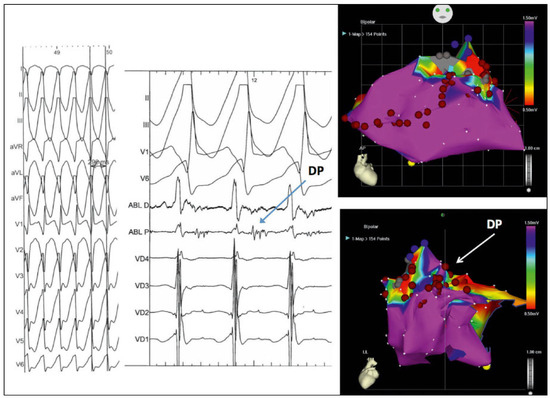

Ventricular Arrhythmias in Congenital Heart Disease: How Can the Electrophysiologist Help?

by Dipen Shah

Cardiovasc. Med. 2017, 20(2), 27; https://doi.org/10.4414/cvm.2017.00459 - 15 Feb 2017

Cited by 2 | Viewed by 72

Patients with congenital heart disease often have ventricular hypertrophy, dilatation and/or fibrosis as part or a direct consequence of their malformation. Moreover, they often have ventricular scars and/or patches and develop secondary haemodynamic overload or valvular abnormalities as a consequence of reparative surgery/interventions [...] Read more.

Patients with congenital heart disease often have ventricular hypertrophy, dilatation and/or fibrosis as part or a direct consequence of their malformation. Moreover, they often have ventricular scars and/or patches and develop secondary haemodynamic overload or valvular abnormalities as a consequence of reparative surgery/interventions that worsen ventricular remodelling. This ventricular remodelling predisposes to polymorphic ventricular tachycardia (VT) or ventricular fibrillation (VF) and sudden cardiac death, as in other forms of heart disease. The presence of an extensive ventricular scar/patch leads to the occurrence of rapid and often poorly tolerated sustained monomorphic reentrant VT, resulting in haemodynamic collapse and even sudden cardiac death. Acute therapy of VT/VF is applicable in accordance with standard guidelines. Chronic management includes reparative therapy of the underlying congenital heart malformation and heart failure treatment, but specific arrhythmia management should ideally be provided by a qualified electrophysiologist who can precisely diagnose the arrhythmia and its mechanism, provide prognostic stratification, determine the substrate, administer specialised electrical therapies including antitachycardia pacing and automatic internal cardiac defibrillation from an implanted device, or perform catheter ablation of the VT substrate. Finally, electrophysiological evaluation can provide valuable information to guide the surgeon to incorporate arrhythmia-neutralising incisions into reparative surgery. Full article

Show Figures

Figure 1